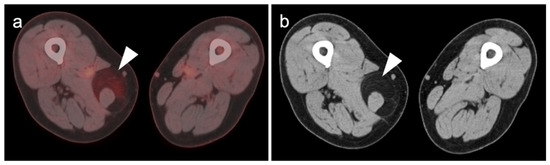

3.1. Soft Tissue Sarcomas

3.1.1. Undifferentiated Pleomorphic Sarcoma

3.1.2. Leiomyosarcoma